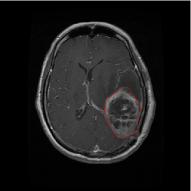

From the above discussions, we have discovered the significant potential of applying Retinex theory to image segmentation and explored its fundamental differences from traditional models. Traditional image segmentation models typically focus on the impact of intensity information on the segmentation results. Therefore, when faced with complex segmentation scenarios, the segmentation results are often affected by lighting, artifacts, and unclear boundaries in the image. As shown in Fig. 1, we present the results of the classical local model LIF [ZHANG20101199] for segmenting brain tumor images along with surrounding tissue edema. The irregular ring-like enhancement caused by the edematous tissue leads to irregular boundaries and low contrast in the images. Consequently, the LIF model can only identify the central necrotic and liquefied regions of the tumor, failing to detect the boundaries and becoming trapped in local minima. In this paper, we draw inspiration from the Retinex theory, which is widely applied in the field of image enhancement. According to Retinex theory, the reflectance component characterizes the intrinsic structural properties of the observed image and preserves texture information independent of illumination variations. By integrating this reflectance component into the level set framework, our model achieves robust segmentation of medical images even under severe intensity inhomogeneity. In addition, a linearized Structural-Prior is proposed to restore intensity consistency and capture local geometric features, thereby improving boundary localization in complex or blurred regions. Furthermore, a relaxed binary level set representation is employed to enhance robustness against noise and to enable accurate tracking of complex contours. Based on these innovations, we propose a novel variational reflectance-based level set model (RefLSM) that simultaneously corrects bias fields and performs segmentation. Experimental results demonstrate that RefLSM significantly outperforms conventional level set methods in both segmentation accuracy and robustness. We present the results of our model segmenting the two brain tumor images mentioned above in Fig. 2.

To address the challenge of segmenting images with severe intensity inhomogeneity, we propose a linearized structural prior that directly operates on the reflectance component . Reflectance-based structural information is more robust to illumination variations and bias field distortions, helping preserve weak edges and subtle anatomical boundaries. As shown in Fig. 2, our method can accurately delineate tumor boundaries and surrounding edema even under severe inhomogeneity, where traditional intensity-based models often fail. The proposed prior aligns smoothed reflectance gradients with data-driven directions, enhancing inter-region contrast, preserving weak edges, and stabilizing the evolution of . Formally, we define the linear structure operator as the gradient field of the smoothed reflectance:

Fig. 4 displays the visual comparison results for segmenting eight brain tumor MR images between the RefLSM and three representative models: the RESLS [8765635], ALF[MA2019201], and L1 model[LIU2019193]. These images exhibit severe intensity inhomogeneity and noise attributable to inconsistent bias field and imaging equipment. The initial level set function (LSF) initialization was consistent across all models, as shown in Fig. 4 (a), which illustrates the initial placement of the zero level contour. For visual clarity, we included the ground truth in Fig. 4 (f). The segmentation outcomes from the RESLS, ALF, and L1 methods are presented in Fig. 4 (b), (c), and (d), respectively.

It is evident from the first and last columns of Fig. 4 (b) that the ALF model tends to become trapped in local minima under severe intensity inhomogeneity. Furthermore, segmentation results presented in the columns 1-4 of Fig. 4 (b) and (c) reveal that both the ALF and L1 models mistakenly segment small isolated or irrelevant regions due to the effects of irregular intensity patterns. Additionally, when weak boundaries are present, as seen in the 1st and 3rd columns of Fig. 4, the RESLS, ALF, and L1 methods fail to accurately identify object boundaries. Consequently, the zero level contours of these models deviate significantly from the objects throughout the level set evolution, causing drastic misalignment after further iterations.

In stark contrast, our proposed method exhibits greater robustness against images exhibiting severe intensity inhomogeneity and weak boundaries. The proposed prior constraint term effectively corrects for intensity inhomogeneity, while the proposed binary level set adeptly reduces noise during the segmentation process.